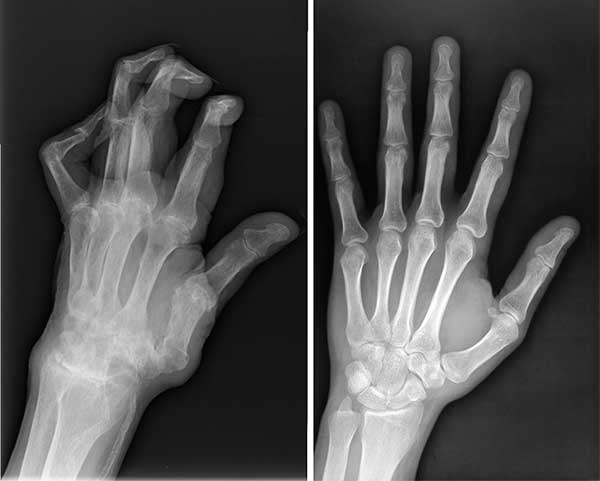

ไม่ใช่แค่หนูคนเดียวที่รอดเพราะผลิตภัณฑ์มหัศจรรย์ตัวนี้ สามีหนูป่วยเป็นโรคข้ออักเสบ ปลายนิ้วเสียหายมาก หนูเลยซื้อ Movinix ให้เขาทาน พวกเราทานด้วยกันแล้วก็หายกันทั้งคู่เลยค่ะ

ภาพเอกซเรย์เปรียบเทียบก่อนและหลังทาน Movinix ของสามี

ภาพเปรียบเทียบสภาพมือของสามีก่อนและหลังทาน Movinix